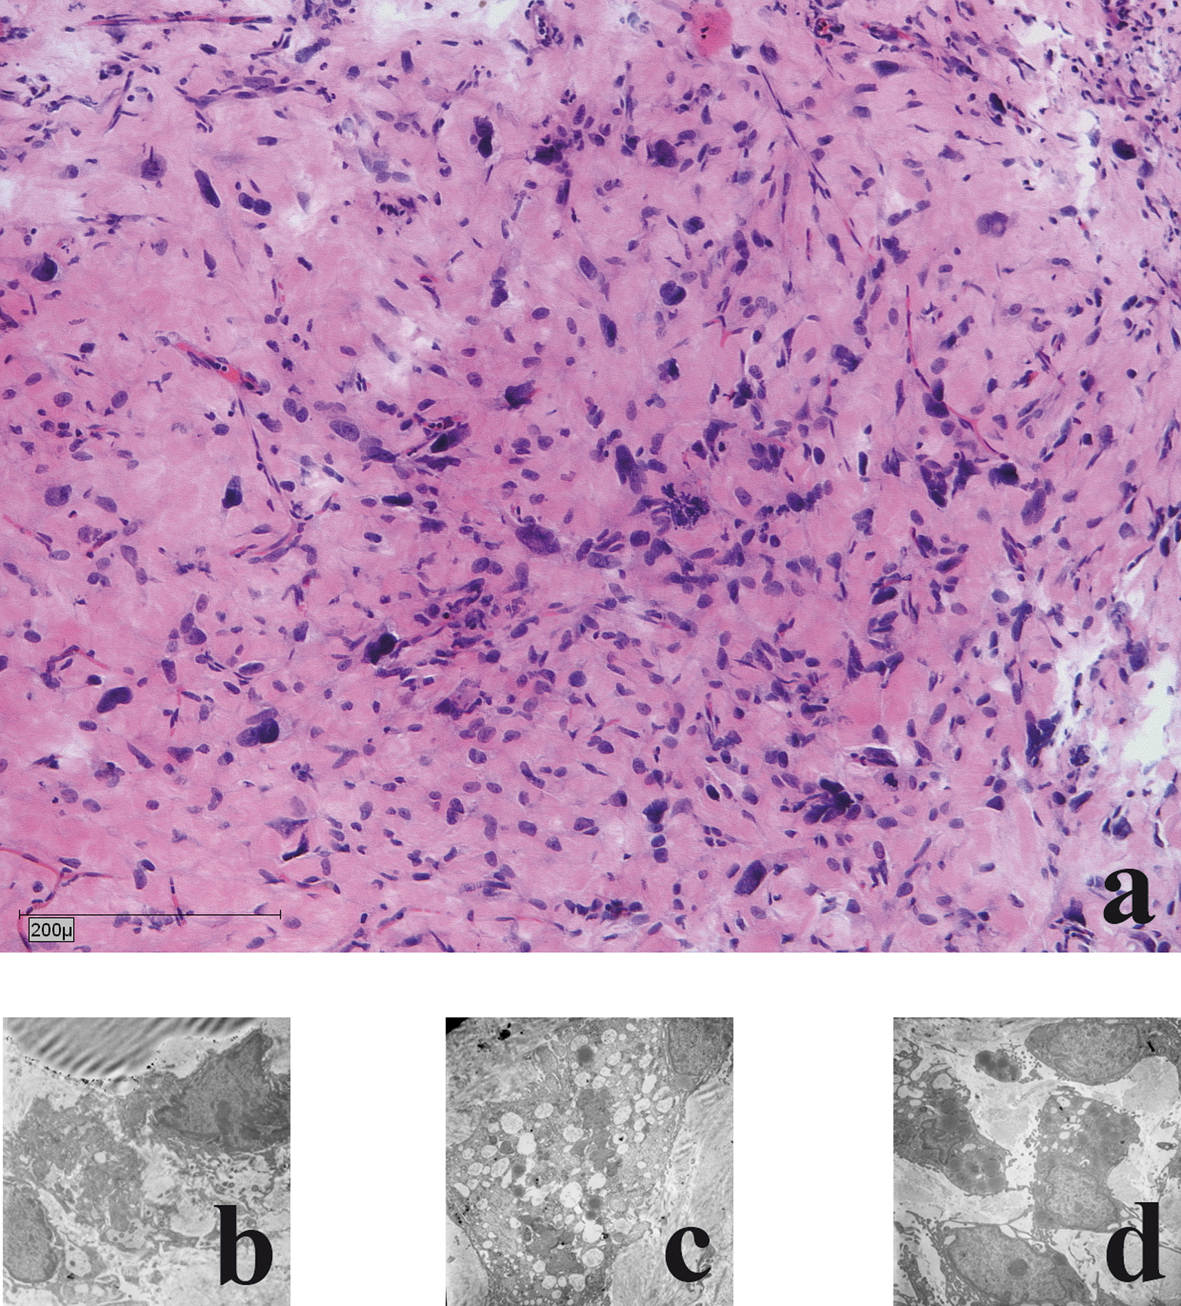

Histological and electronmicroscopical morphology of the xenotransplants

In all cases (n = 6) the liposarcomas in the chamber model demonstrated a moderate, partial severe inflammation with giant cells was detectable. All cases showed circumjacent to the tumour, slight to moderate proliferations of fibroblasts (Fig 3a). Ultrastructural maintenance was good in the tumour grown in the chamber. Heterogeneity of tumour cells and nuclei was seen with irregularities of nuclei. Focally necrotic areas were seen. Heterogeneity of tumour cells and nuclei was seen with irregularities of nuclei and many small nuclei. Cell necrosis and cell disintegrations were common findings (in more than 50%) (Fig. 3b-d).

![]() Click for large image | Figure 3. Histological and electronmicroscopic morphology of the xenograft: a) haematoxylin and eosin staining; b) Nuclear morphology demonstrates large oval atypical cell nuclei with heterochromic prominent nucleoli; c) Lipid vacuoles: few light and dark vacuoles with no accumulation of glycogen; d) Cytoplasm: few reticular endoplasmic reticuli with few dark elongated elliptical mitochondria. |